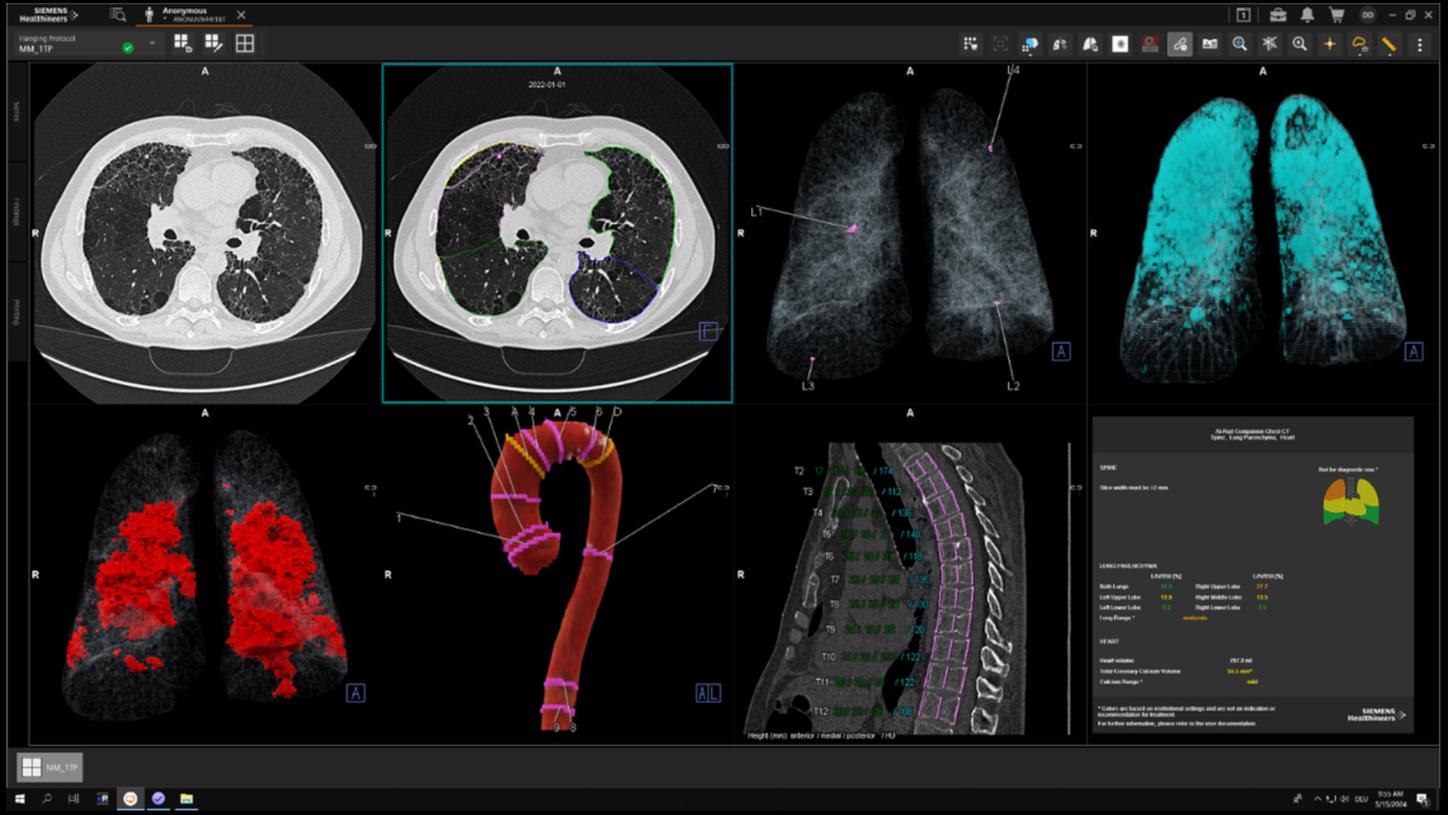

14) Data on file. B Maldera A, et al. (2016): Digital breast tomosynthesis: Dose and image quality assessment; For average breast size of 50/50 glandular/adipose tissue and 5 cm thickness

17) AI-Rad Companion Chest CT is not commercially available in all countries. Future availability cannot be ensured.

18) Lee C, Nagy PG, Weaver SJ and Newman-Toker DE: Cognitive and System Factors Contributing to Diagnostic Errors in Radiology. https://www.ejradiology.com/article/S0720-048X(20)30614-8/fulltext